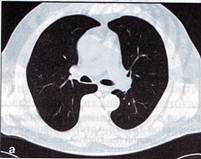

1. Определите метод лучевой диагностики и плоскость исследования.

2. На предыдущих снимках определите анатомическую область применения метода лучевой диагностики.